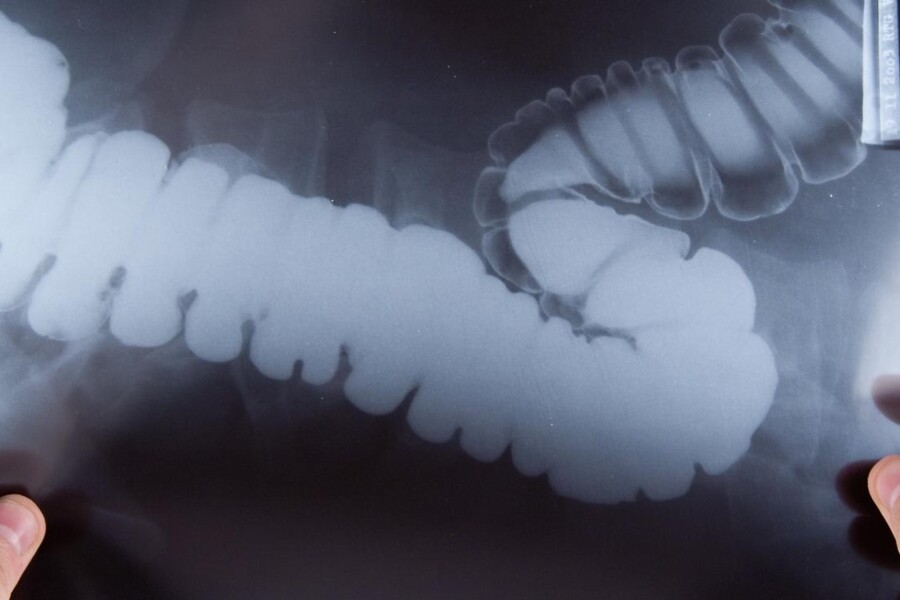

Lékař dítěti vyšetří konečník, aby si ověřil, zda neobsahuje stolici. Na základě výsledků prostého rentgenu břicha a rentgenu s bariovou náplní zjistí, zda došlo k zúžení tračníku. Bývá také nutné manometrické vyšetření. Normální nucení na stolici způsobuje tlak v tračníku vyvolaný stolicí nebo plyny. Při manometrickém vyšetření se měří reakce svalů kolem řitního otvoru na tlak v konečníku pomocí přístroje zvaného manometr. Diagnózu Hirschsprungovy nemoci potvrdí vzorek tkáně odebraný z konečníku, který neobsahuje nervové buňky.